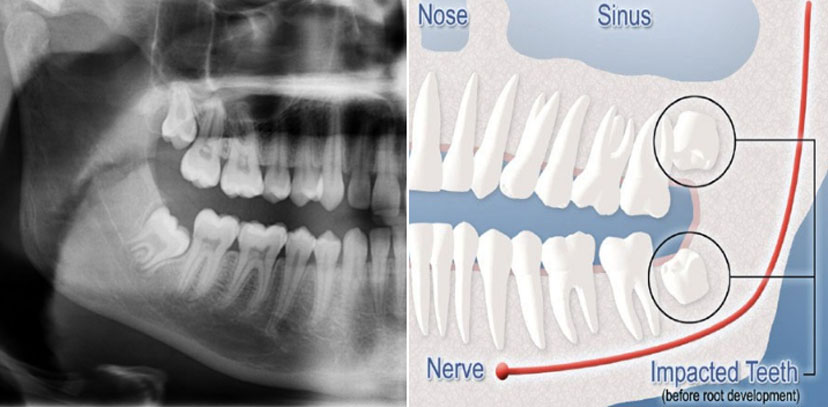

When teeth are physically prevented from erupting, they are considered to be impacted. Impacted teeth cannot erupt into the proper position for chewing and cleaning. Impaction occurs when the tooth is positioned against another tooth, bone, or soft tissue, and prevents the tooth from fully erupting from the gums into a healthy position. This is a common problem affecting 75% of the population and can lead to other issues if the tooth remains untreated.

There are four common classifications of impactions – soft tissue, partial bony, complete bony, and complete bony impacted difficult.

Panoramic view of the jaw showing wisdom teeth and other anatomical details.